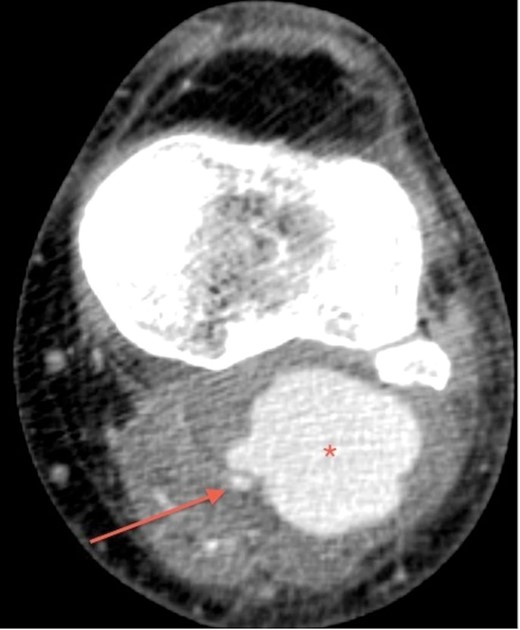

His laboratory reports for full blood count, urea and electrolytes were normal. In view of the ultrasound findings, a CT angiogram of lower limbs was performed. It confirmed 6 × 5 × 4 cm pseudoaneurysm, compressing and displacing his left popliteal artery. However, three-vessel run-off below the knee was satisfactory (Figs 1 and2).

CT angiogram of the left leg, transverse section, shows popliteal pseudoaneurysm (asterisk) adjacent to the popliteal artery (arrow).